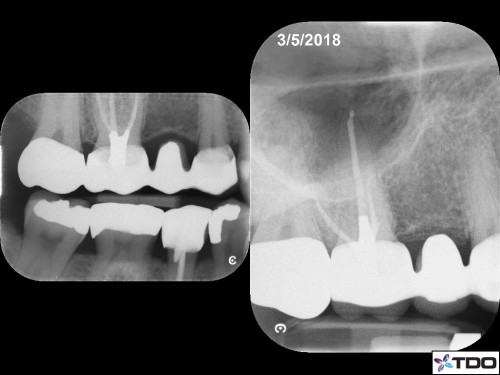

42 yom.

Symptomatic Partially Vital Pulp. No response to cold. Upon access, I observed hyperemic tissue in MB1 and partially vital tissue in the rest of the canals. 2-1-2 MB root system. 1 visit.

Asymptomatic and functional at the follow-up visit.

The treatment was a successful Root Canal Therapy performed in one visit on a tooth suffering from symptomatic Irreversible Pulpitis with complex canal anatomy (MB1 and presumably MB2 were found). nelnet com